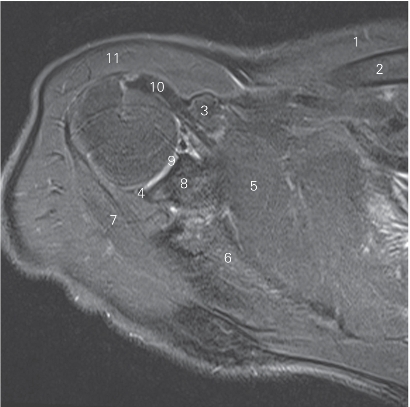

图4-9 经肩关节盂唇的横断层MR T2WI FS

1 胸大肌 pectoralis major 2 喙肱肌 coracobrachialis

3 前盂唇 anterior glenoid labium 4 肩关节 shoulder joint

5 关节盂 glenoid cavity 6 冈下肌 infraspinatus

7 后盂唇 posterior glenoid labium 8 肱骨头 head of humerus

9 肱二头肌长头 long head of biceps brachii

10 三角肌 deltoid